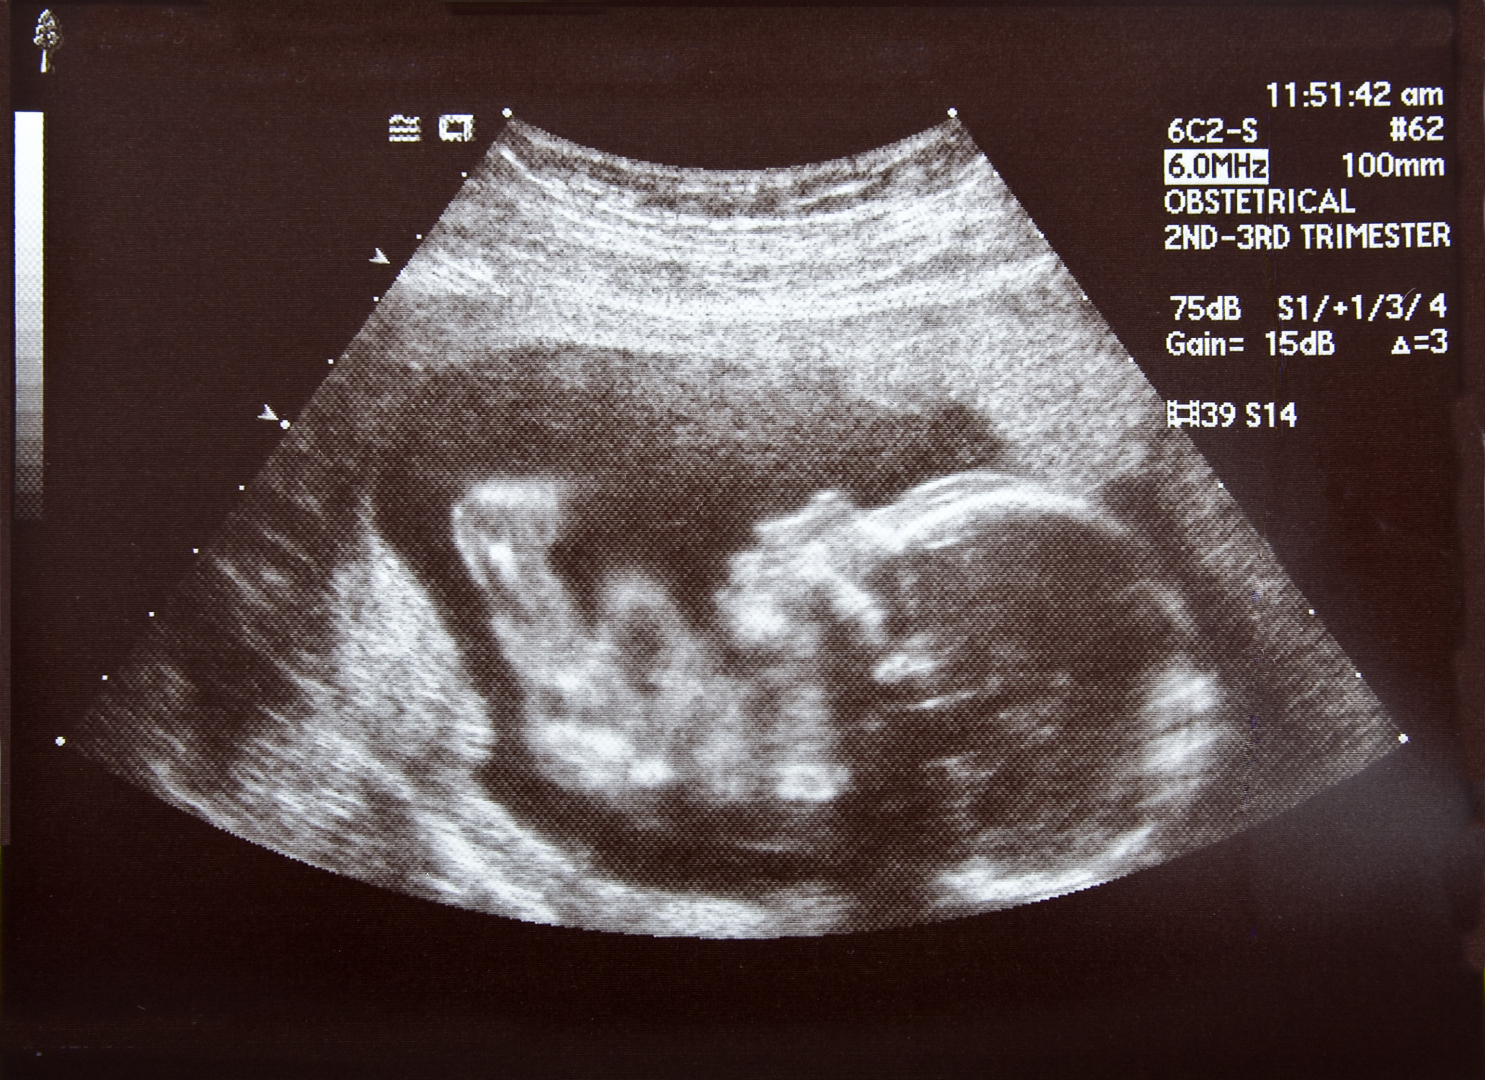

Impact of occupational exposure to solvents during pregnancy on fetal growth

Enderle I, De Lauzun V, Metten MA, Monperrus M, Delva F, Blanc-Petitjean P, Dananche B, Paris C, Zaros C, Le Lous M, Béranger R, Garlantézec R. Maternal occupational exposure to organic solvents and intrauterine growth in the ELFE cohort. Environ Res. 2023 May 1;224:115187. doi: 10.1016/j.envres.2022.115187. Epub 2022 Dec 29. PMID: 36587719.